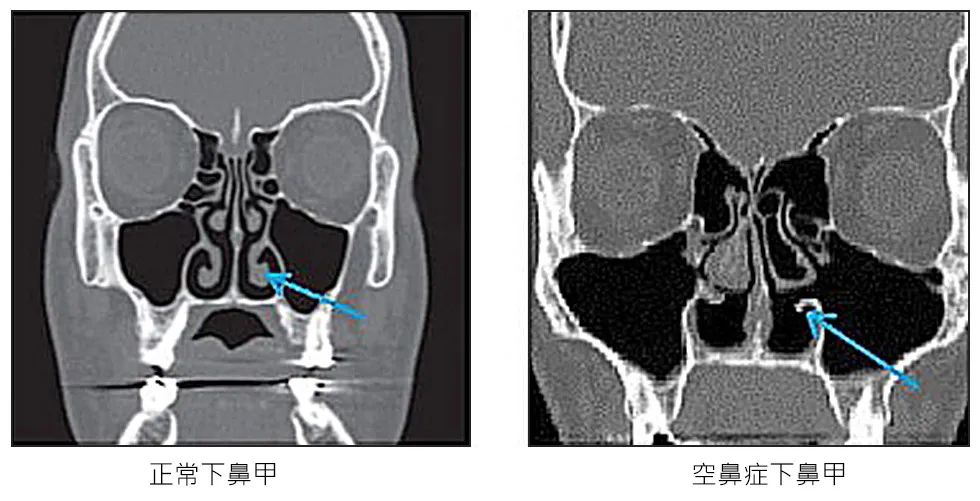

箭头所指即为缺失的下鼻甲 图源:iskin.com

近年来越来越多的研究报告表明,空鼻症是由于人体感应到鼻腔中异常的压力与温度引起的。位于鼻甲上的压力或温度感受器如果被手术破坏,就可能导致某些人失去感知鼻呼吸的能力。